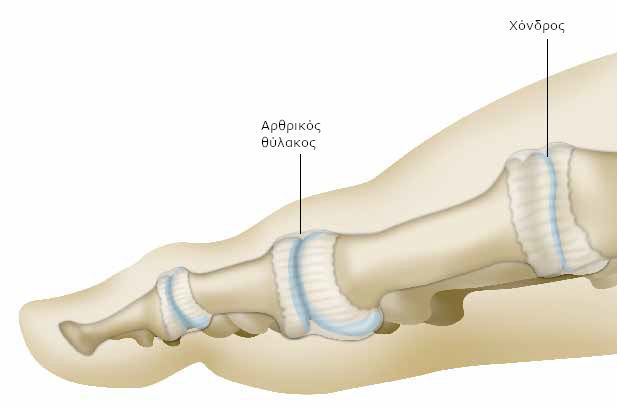

Μια σχετικά μαλακή επιφάνεια (ο χόνδρος) καλύπτει τις άκρες των οστών και διευκολύνει την ολίσθηση μεταξύ τους.

Η άρθρωση περιβάλλεται από έναν ινώδη σάκο (τον αρθρικό θύλακο) και ελαστικούς ιστούς (τους συνδέσμους), που επιτρέπουν τη συγκράτηση των δύο οστών σε ένα σταθερό άξονα.